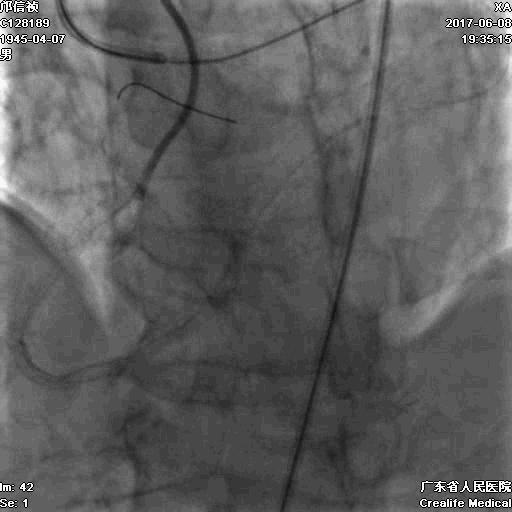

1.正向2.5*15mm球囊扩张,Reverse CART

2.Guidezilla延长导管辅助下,逆向导丝进入正向GC

1.更换RG3导丝

2.GC送入普通导丝,保护LM

支架术后造影结果